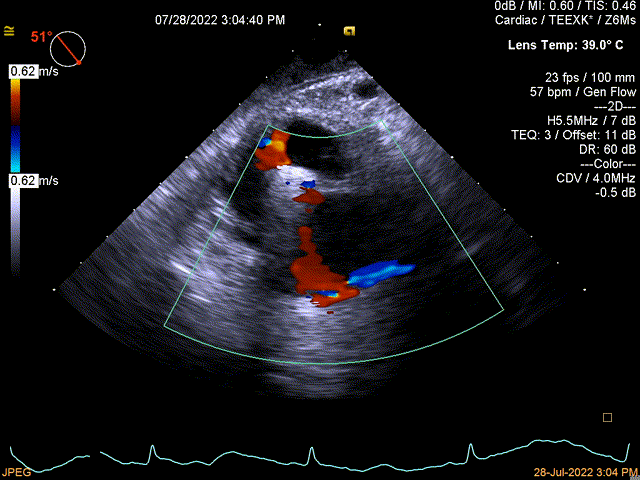

图1:术前TEE

术前TEE提示三尖瓣瓣叶活动尚可,无明显脱垂,隔瓣较短,反流束来源于后瓣及隔瓣交界处,后瓣及隔瓣对合缘保留良好,反流束同时向前隔交接延伸。